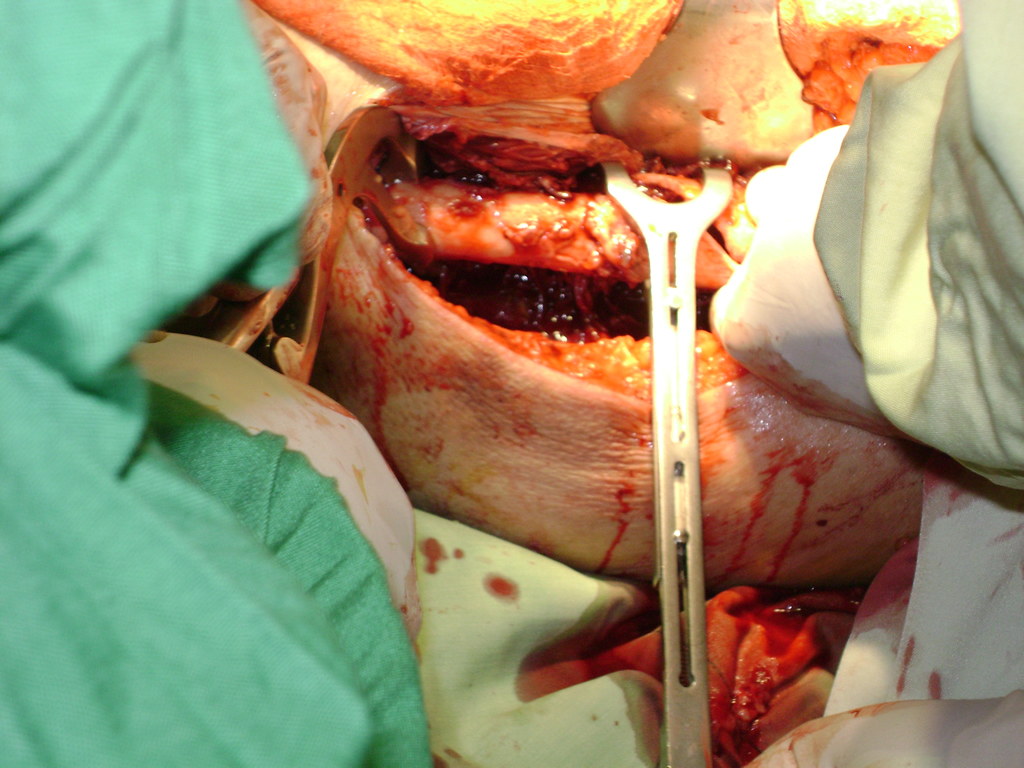

La cirugía de fractura de cadera se realiza para reparar una ruptura en la parte superior del hueso del muslo. Este hueso se denomina fémur.

A menudo se recomienda la cirugía para reparar la fractura debido a dichos riesgos.